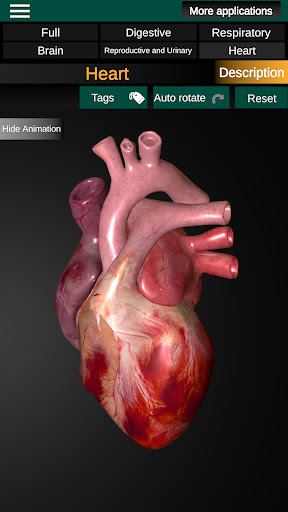

* Hart, dat de atria, ventrikels, aorta en een animatie van dit orgel omvat.